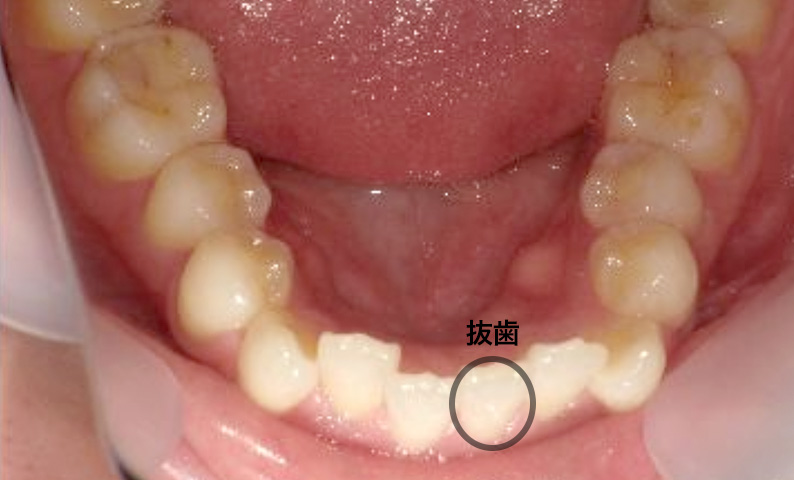

症例_004 下顎だけの部分矯正

治療期間:7ヶ月金額:24万円+税男性前歯のガタガタ下の前歯だけ

| Before | After |

|---|---|

|